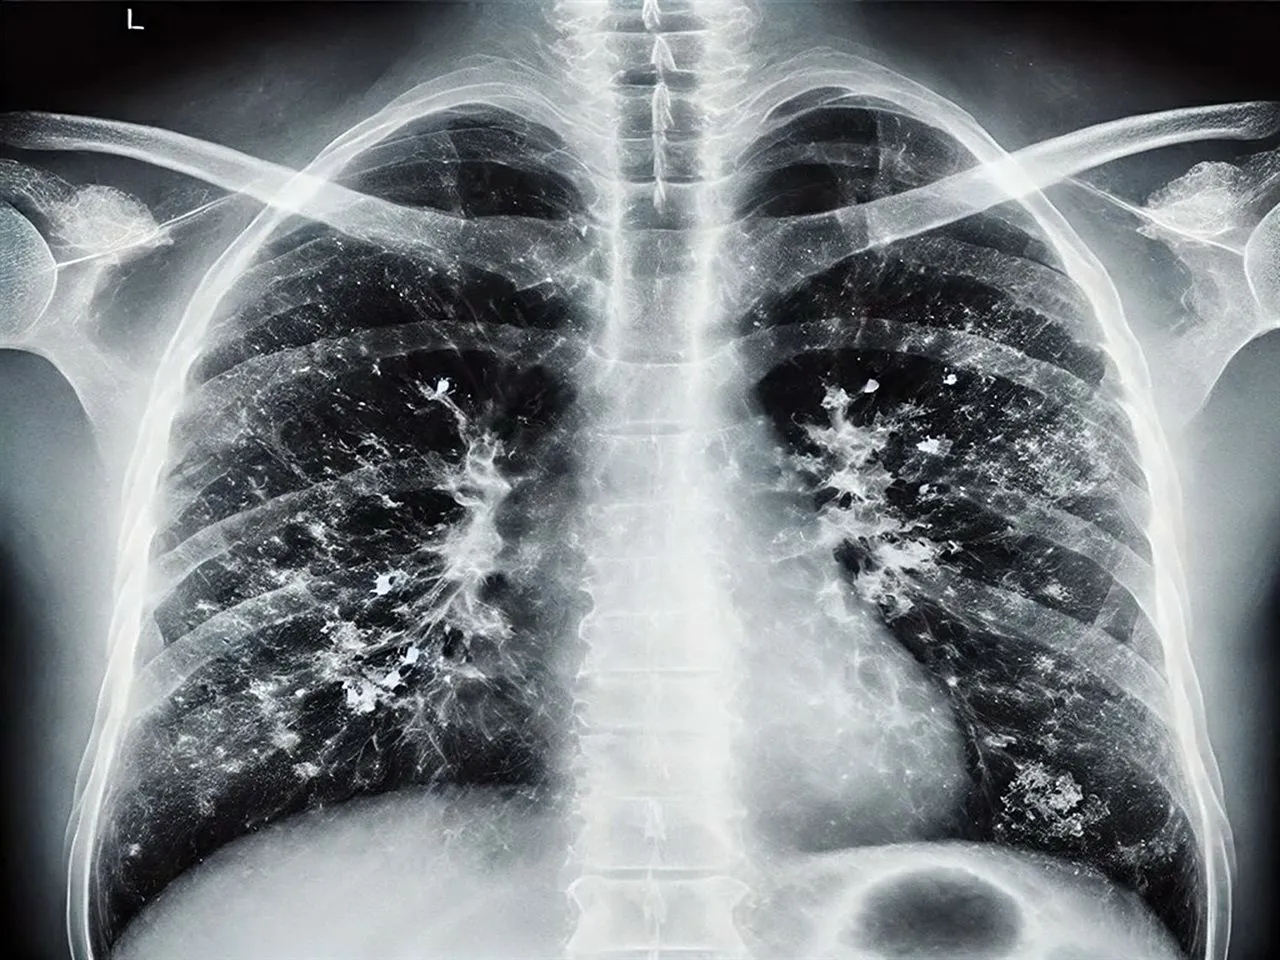

İKÇÜ Atatürk Eğitim ve Araştırma Hastanesi Enfeksiyon Hastalıkları Anabilim Dalı'nda görevli Prof. Dr. Alper Şener, son dönemde viral enfeksiyonlarda artış yaşandığını belirtti.